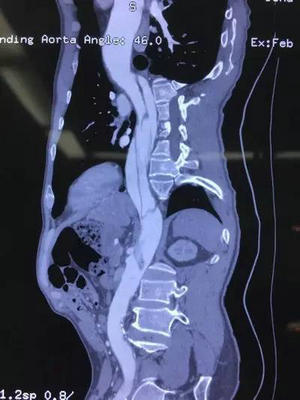

今年57岁的董先生突发胸背部疼痛,在当地医院诊断为胸主动脉夹层,急诊由120转入血管外科。治疗难点在于主动脉破口紧贴左侧锁骨下动脉,且左椎动脉优势,夹层向远端螺旋形撕裂至左侧股动脉,右侧髂动脉闭塞,右肾动脉双腔供血,左肾动脉假腔供血,肠系膜上动脉双腔供血,真腔近闭塞,存在急性肾功能衰竭、肠坏死及下肢缺血坏死风险!

术前CTA